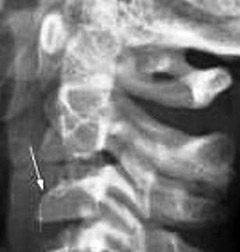

pediatric spine - Copyright – Stock Photo / Register Mark Figure 1: The space between the lateral masses relative to the dens can be < 6 mm, but the lateral masses of C1 can still remain aligned with the lateral masses of C2 in the pediatric spine. The vertebrae of C3 through C7 can be discussed as a group because they demonstrate the same developmental pattern. There are three primary ossification sites for each vertebral segment: the vertebral body, which develops from a single ossification center, and two neural arches. The neural arches fuse posteriorly by age 2-3 years and the body fuses with the neural arches between 3-6 years of age. In addition, there are secondary ossification centers at the tips of the transverse processes and spinous processes that may persist until early in the third decade of life, simulating a fracture. The secondary ossification centers at the superior and inferior aspects of the cervical vertebral bodies, the endplates, can remain unfused until early adulthood.

Pseudo subluxation - Copyright – Stock Photo / Register Mark Figure 2: Pseudo subluxation at the C2-3 level; note that the spinolaminar line remains contiguous. Distance Between the Dens and Lateral Masses (Pseudo-Jefferson Fracture): The pseudo-spread of the atlas on the axis (pseudo-Jefferson fracture) is seen on the APOM view. Displacement up to 6 mm of the lateral masses relative to the dens is common up to the age of 4 years old, but can be seen up to 7 years of age. (Figure 1)